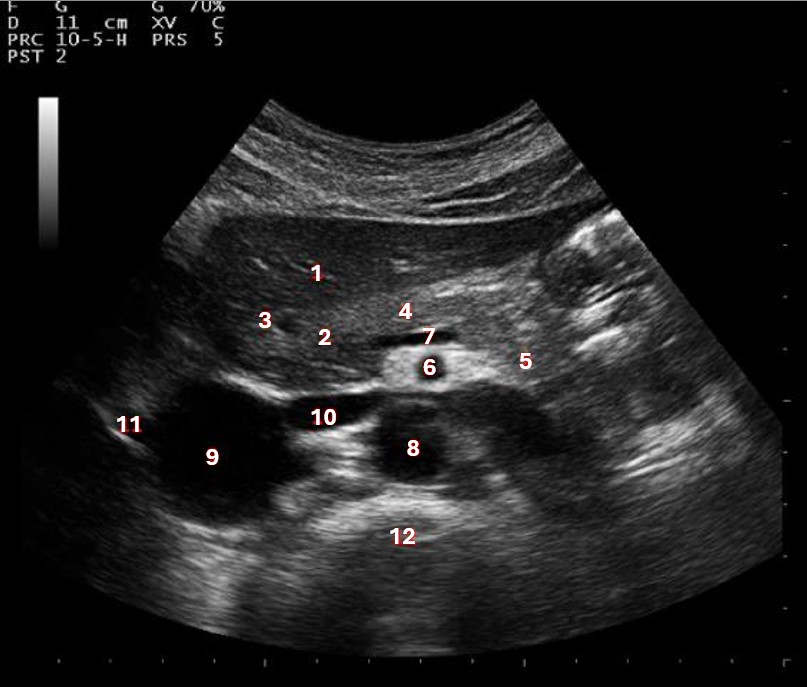

Which of the following structures is labeled number #1?

Left hepatic vein

What structure/vessel is indicated by #3?

Gastroduodenal artery

What structure/vessel is indicated by #2?

Head of pancreas

What lobe of the liver is indicated by #1?

Posterior right lobe

Which of the following structures is labeled #2?

Middle hepatic vein

Which of the numbered vessels is part of the portal system?

2

What structure/vessel is indicated by #1?

Medial branch of LPV

Left portal vein

Which of the following structures is labeled #3?

IVC

Which of the following structures is labeled #6?

Medial left lobe

What structures last vessel is indicated by #4?

Which of the following structures is labeled #4?

Right hepatic vein

Which structure/vessel is indicated by #5?

Lateral left lobe

Which of the following structures is labeled #8?

What structure/vessel is indicated by #12?

Spine

Which structure/vessel is indicated by #4?

Body of the pancreas

Lateral branch of LPV

What structure/vessel is indicated by #7?

Splenic vein